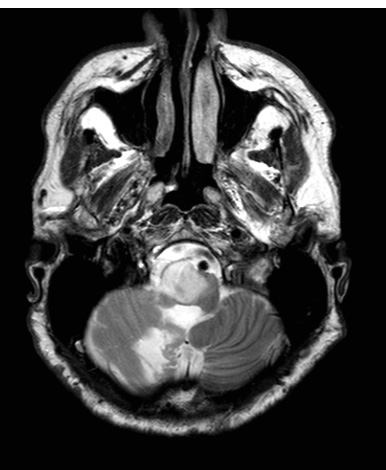

3A2 HGAP (Case 3) T2noC - Copy

The extent of the tumor is shown on this T2-weighted no applied contrast scan.